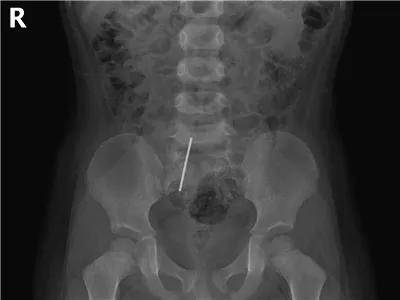

硬币的一场“旅行”

硬币是儿童消化道异物中最最最常见的。虽然有些孩子可以自行排出,但是部分幼龄患儿仍需手术取出。家长还是当心点吧!

到直肠啦,肛门口上方了,此时硬币为侧影,因而呈条柱状。